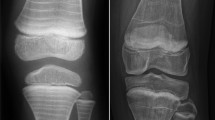

The current diagnostic criteria of JO were established in 2013 according to the ISCD. The presence of a non-traumatic vertebral compression fracture (> 20% loss of vertebral height ratio) regardless of BMD or the coexistence of a history of clinically significant fractures (≥ 2 long bone fractures by the age of 10 years, or ≥ 3 long bone fractures by 19 years) with a BMD Z-score of ≤ − 2.0 are mandatory for the diagnosis of JO [4]. According to these recommendations, densitometry criteria alone are not adequate in the diagnostic work-up of JO. Indeed, the occurrence of fragility fractures with concomitant BMD Z-scores > − 2.0 was found in children with osteopenia-inducing diseases, such as leukemia, neuromuscular disorders, or rheumatic disorders [26, 32,33,34]. A further limitation of BMD assessment is the disparity in Z-scores generated by different pediatric reference databases. In 2015, the Canadian STOPP Consortium observed a significant disparity among different BMD Z-score databases used in a cohort of 186 children with leukemia and vertebral fractures, upholding the lack of validity of the BMD Z-score threshold alone in the definition of JO [32]. Moreover, areal BMD (g/cm2) can underestimate volumetric BMD (g/cm3) in children with short stature and overestimate BMD in taller ones. The use of bone mineral apparent density (BMAD) and height-for-age Z-score (HAZ) BMD represent valid tools to minimize stature impact on BMD [35]. Peripheral quantitative computed tomography (pQCT) may provide further advantage compared with DXA, as the measures obtained by this three-dimensional technique are not influenced by bone size. Furthermore, pQCT is capable of evaluating trabecular and cortical bone distinctly. However, the use of pQCT remains confined to the research field due to lack of reference data and scanning acquisition consensus [36]. Total body less head and lumbar spine are the preferred regions of interest for DXA assessment in pediatric patients as confirmed by ISCD in 2013 [36]. On the other hand, DXA assessment at other skeletal sites such as distal forearm, proximal femur, and lateral distal femur were suggested in patients with severe scoliosis or other skeletal anatomical disorders, according to updated 2019 guidelines [37]. On these bases, a careful diagnostic approach is primarily based on an accurate clinical evaluation including fracture location (with particular attention to vertebral fracture surveillance), magnitude of trauma, family history, and the presence of other risk factors. Recently, Ward et al. proposed an algorithm for the differential diagnosis of osteoporosis in children, which aims to explore genetic and metabolic defects, as well as underlying acute or chronic illnesses [2].